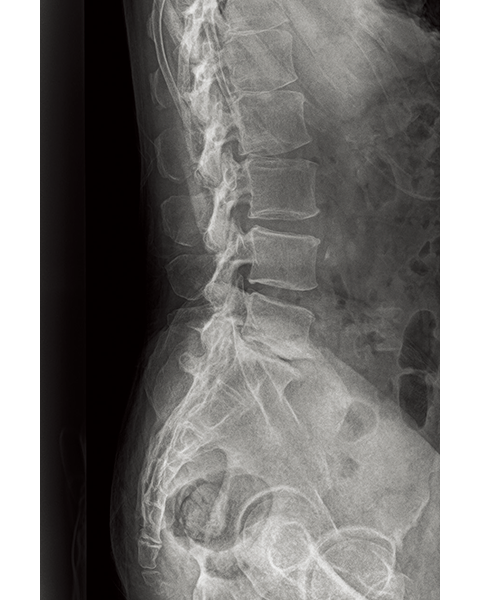

Dynamic Visualization II

Optimizes image quality using latest Exposure Data Recognizer

Advanced recognition algorithms using automatic  calculations of estimated 3D image data, identify the body part required and adjusts contrast, density and enhancement for optimised image display. (Option)

Comparison of Dynamic Visualization II vs. conventional processing images (Lumbar Spine)